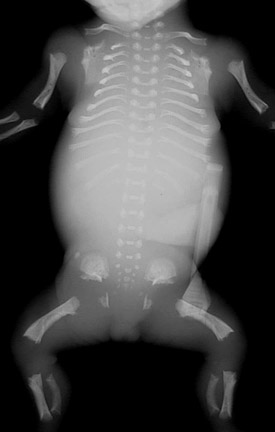

| Ultrasound may reveal long bones that are shortened. There are several possibilities, including short-limbed dwarfism. Seen here is a radiograph demonstrating short, curved femora and humeri, along with prominent platyspondyly of the vertebrae. This is thanatophoric dysplasia. As the name implies, this is a lethal condition, but it occurs sporadically. Achondroplasia is another form of short-limbed dwarfism that is an autosomal dominant condition which is lethal in the homozygous form. |